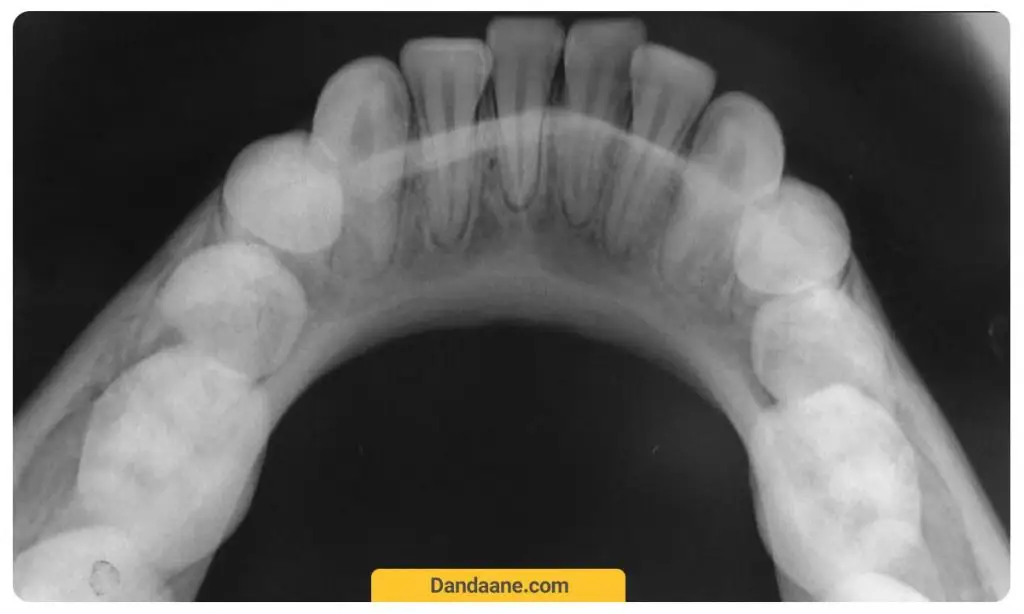

1. هزینه عکسبرداری از دندان

اصولا قبل از جرم گیری، دندانپزشک برای بررسی بهتر تصویربرداری از دندان ها را توصیه می کند. بنابراین هزینه عکسبرداری دندان در کنار هزینه جرمگیری دندان محاسبه می شود.

برخی بیماران تنها به منظور جرمگیری به مطب دندانپزشکی مراجعه می کنند اما پس از گرفتن عکس او پی جی یا سایر تصاویر رادیولوژی پزشک مربوطه متوجه پوسیدگی دندان ها، بیماری های لثه و … می شود. بنابراین در صورت وجود چنین بیماری هایی هزینه آنها به هزینه جرم گیری دندان اضافه می شود.